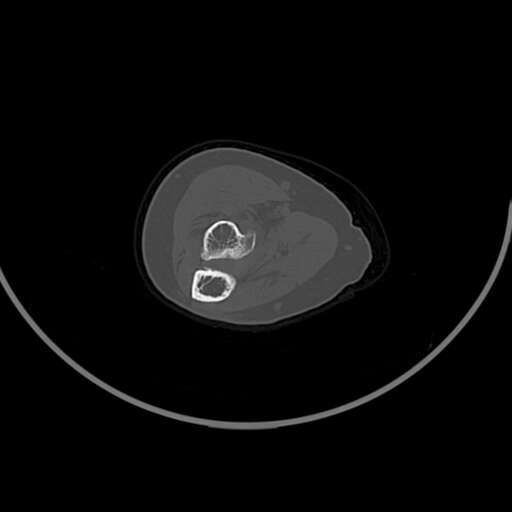

左肘部肿物

女83岁,

符合骨软骨瘤

良性病变。请结合临床。软骨岛、骨瘤或骨膜反应性增生、局部骨梗死都可以这样。